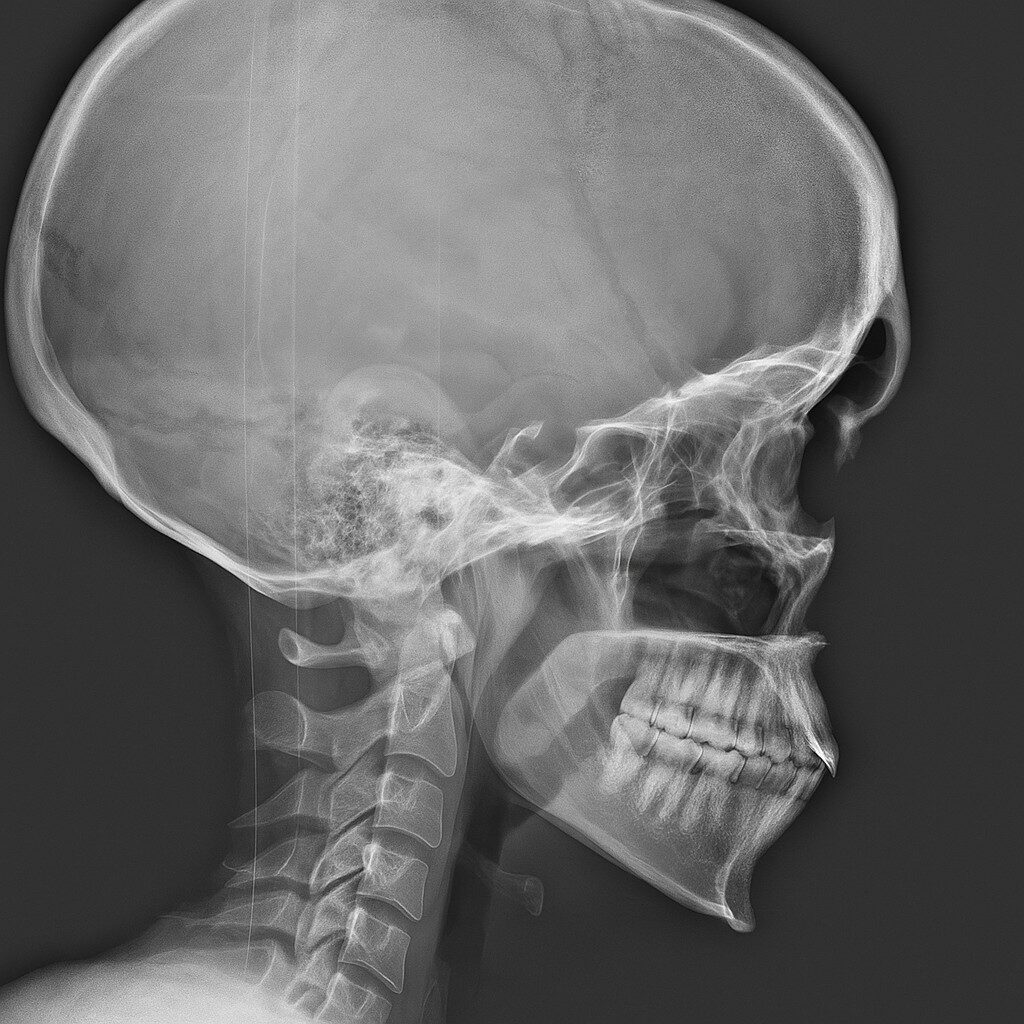

Praxisnahe Röntgenfälle, strukturierte Befundung, fundiertes Fachwissen. Lernen, üben, anwenden — mit echten Fällen aus der klinischen Praxis.

Die spezialisierte Lernplattform für Projektionsradiographie. Im Mitgliederbereich steht eine stetig wachsende Fallsammlung mit realen Röntgenbildern zur Verfügung — systematisch aufgebaut, mit strukturierter Befundung, Befundcheck und klinisch relevanten Zusatzhinweisen.